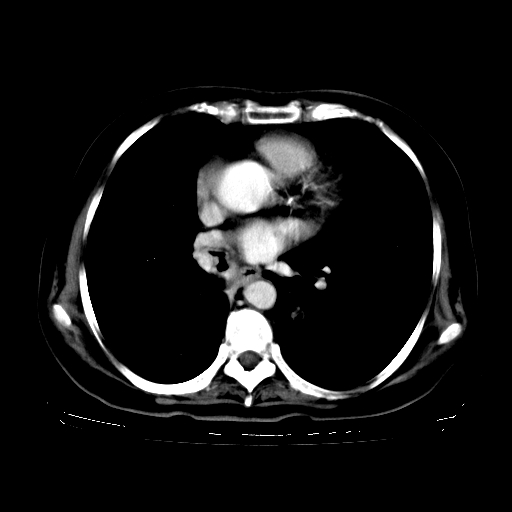

2.胸主动脉夹层。

支持,首先一元论解释。胸主动脉部分层面环形低密度,中心强化。环形影不强化。不象真假腔的改变。我考虑动脉炎,不太支持夹层动脉瘤-和大家的观点不一致,希望楼主让患者再做个心血管的彩超吧。

继发型肺结核,右下肺支气管内膜结核.右侧少量胸腔积液.主动脉夹层.

支气管内膜结核肺内播散.右侧少量胸腔积液.主动脉夹层.